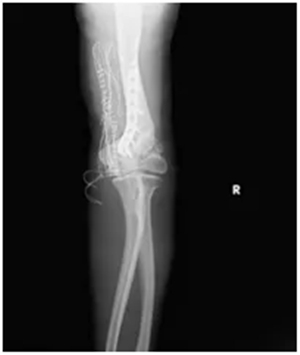

肘关节外翻角度从术前的30°左右,成功矫正到10°左右;

X线复查显示:钢板固定位置十分合适,骨头对位良好;

第二步“肱骨截骨矫形+钢板固定”:通过精准截骨,纠正肘关节的外翻畸形,再用钢板牢牢固定,让关节恢复正常的力学结构。